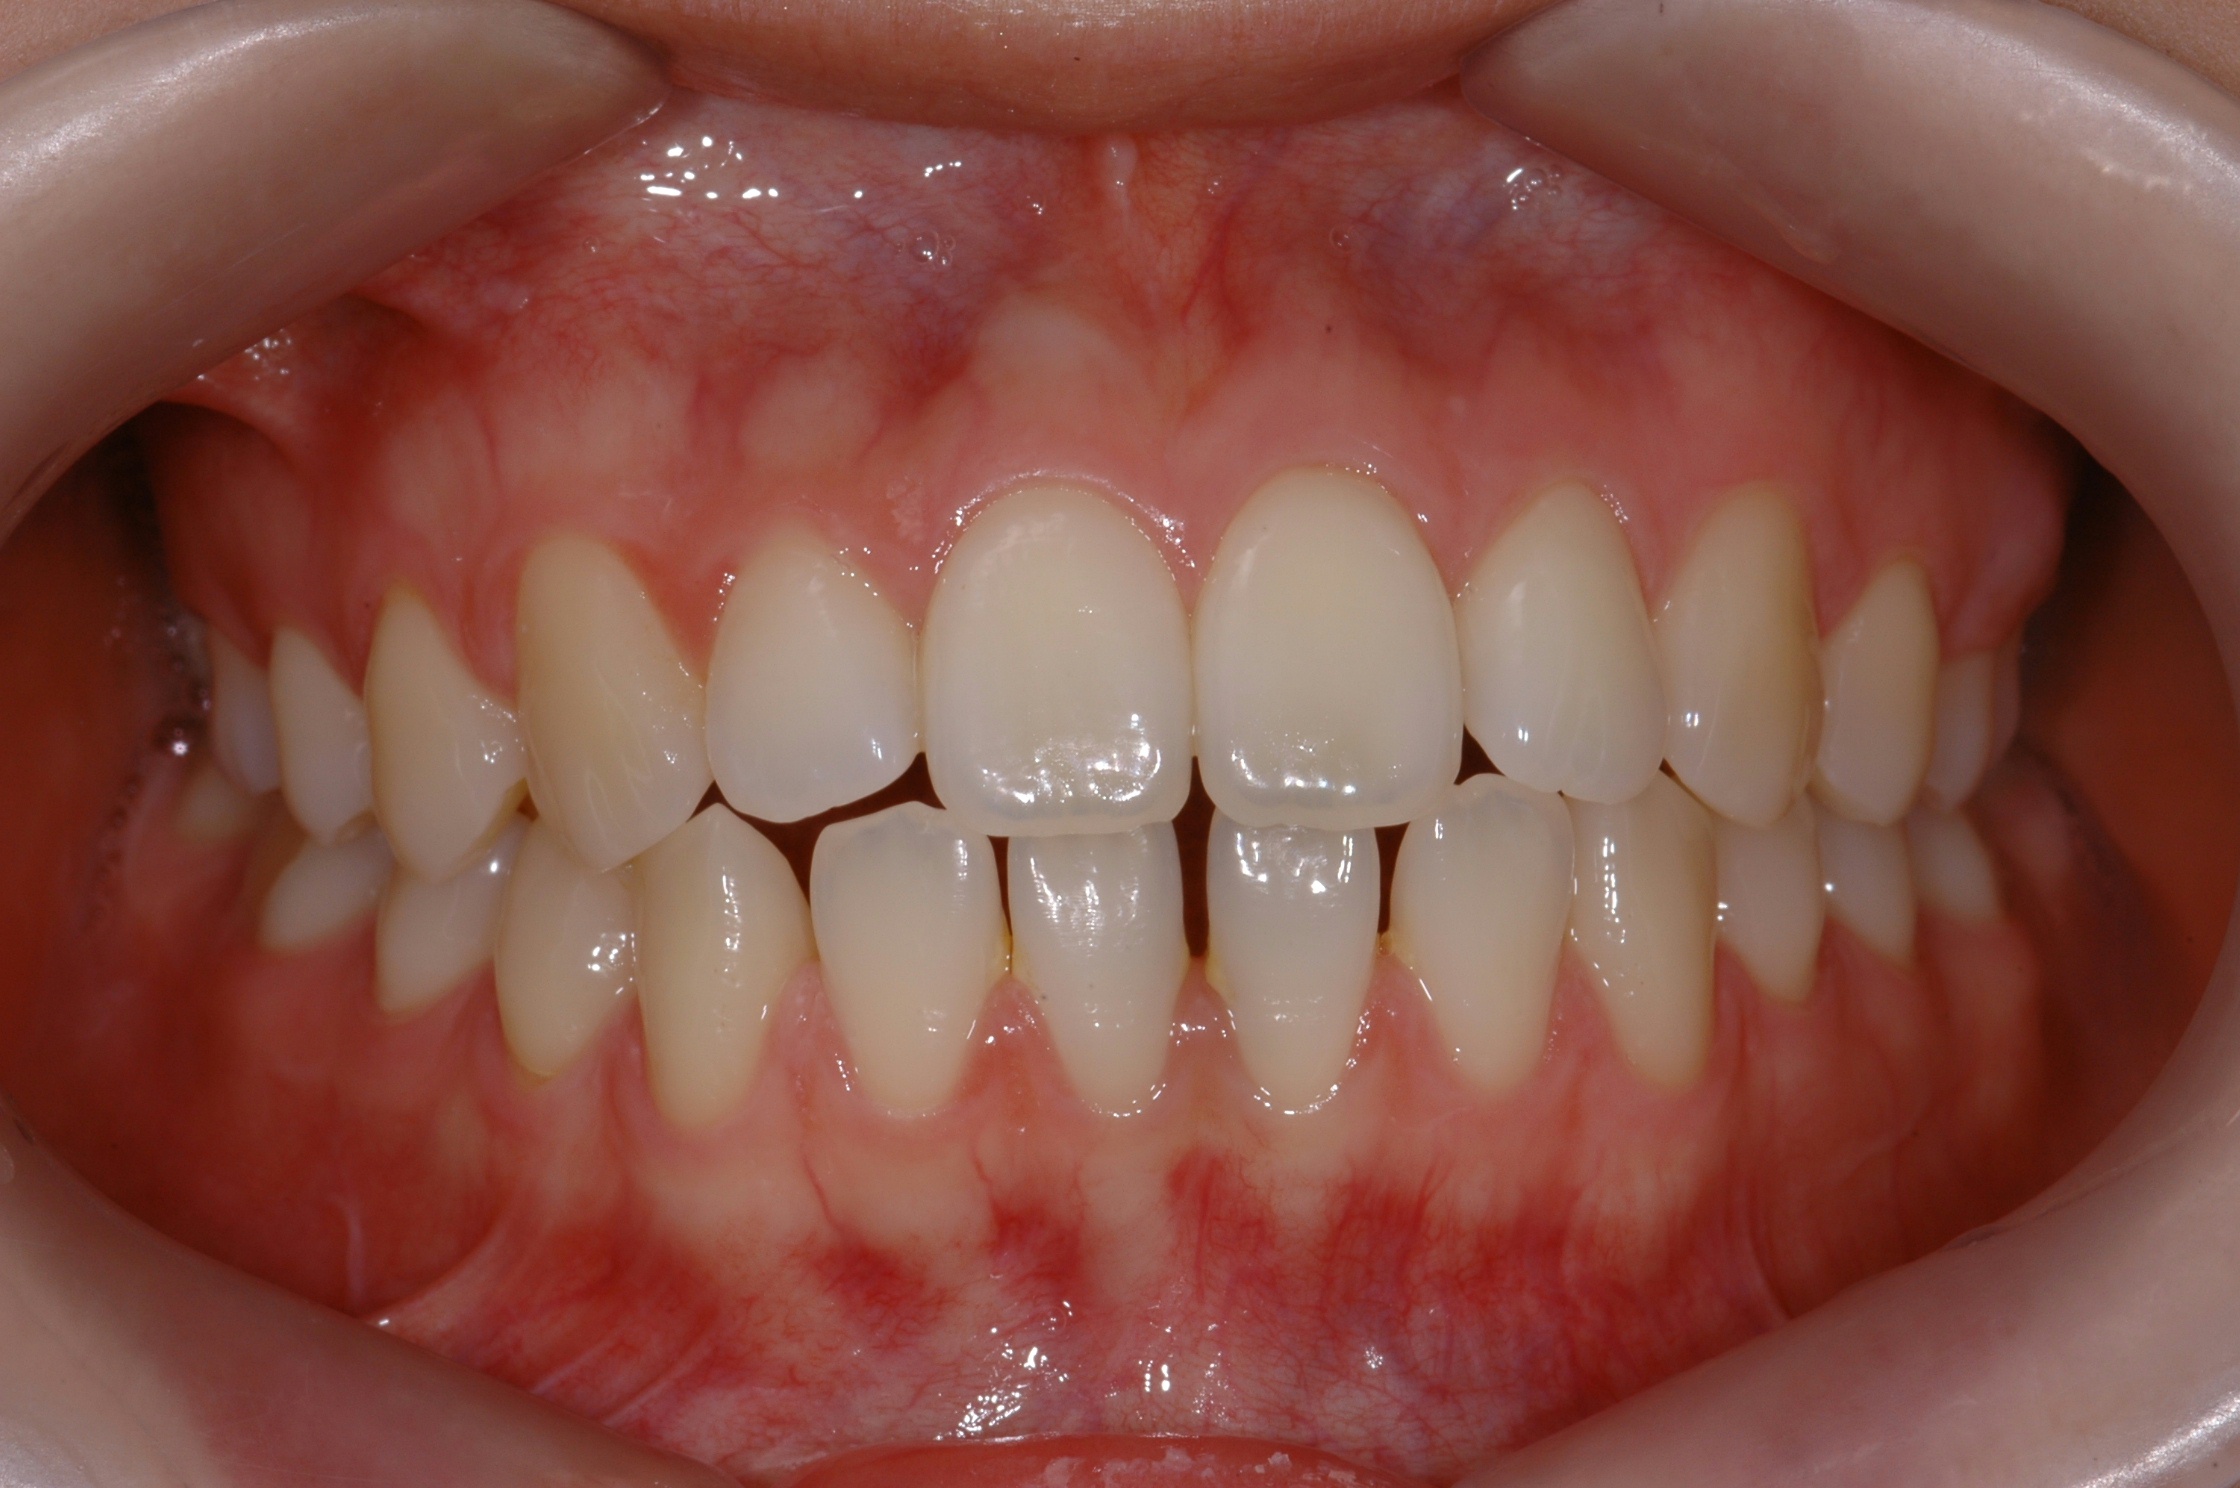

치료 전 사진입니다.